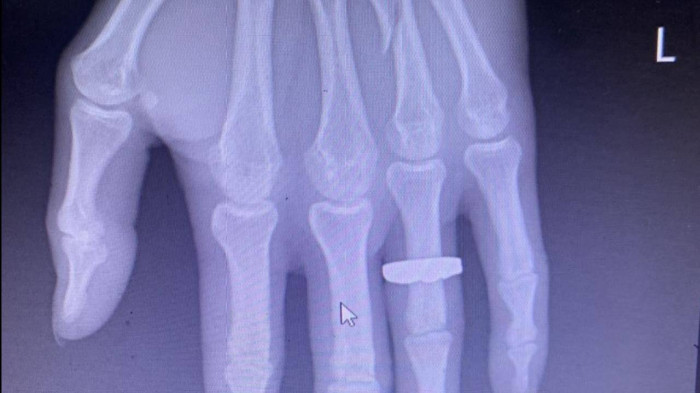

Hình ảnh xương ngón tay áp út bàn tay trái của anh Sáng bị đánh gãy

Nội dung bài báo phản ánh việc ngày 30/10, anh Hồ Mủn Sáng (SN 1985, trú tại tổ 1, khu 5, phường Hải Yên, TP Móng Cái, Quảng Ninh) đã bị phụ xe, tài xế trên chiếc xe khách tuyến Hà Nội – Quảng Ninh mang BKS 14B-042xx hành hung dã man làm gãy ngón tay, chấn thương nhiều vị trí trên vùng mặt, đầu...